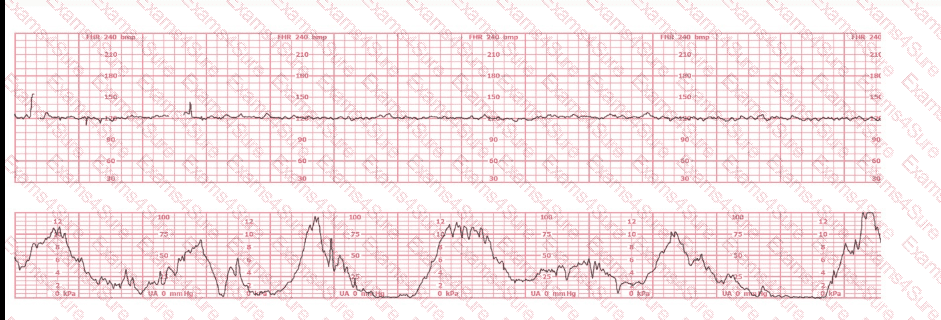

A woman (G1, P0) at 41-weeks gestation presents to OB triage to rule out labor. Her cervical exam is 1 cm/50%/-2. Membranes are intact. She would like to go home if not in labor. Based on this tracing, which represents the last two hours, the best approach is: